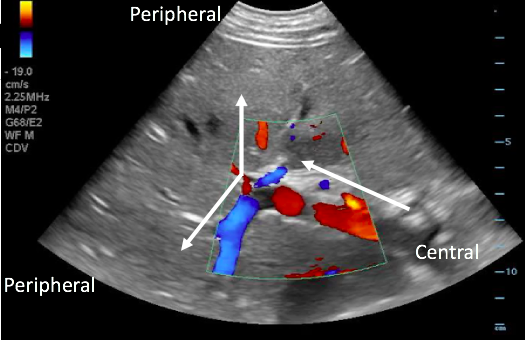

- With the probe on the anterior abdominal wall, blood in the portal vein flows from central (the mesenteric and splenic veins) towards the liver and will be red when color Doppler is applied. The middle and left portal venous branches will still appear red. However, blood in the right portal venous branch will flow deep into the right lobe, appearing blue.

Figure 17. Color Doppler image with arrows illustrating normal portal venous blood flow, from the center towards the periphery of the liver.